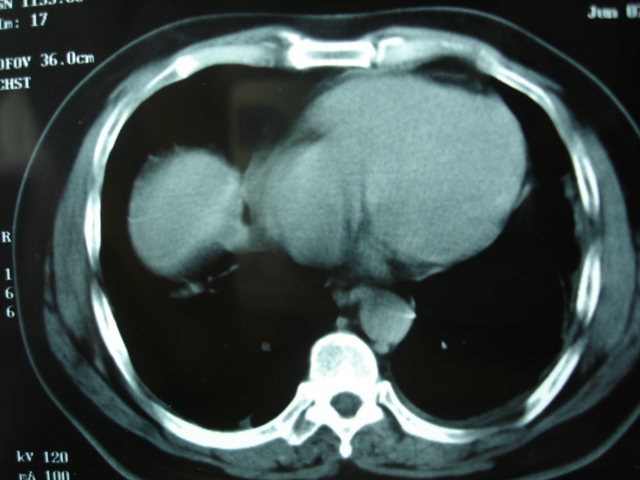

2009.6.4 2009.6.7 2009.8.21

第三次ct2009.8.21

炎症,最厚一次已吸收